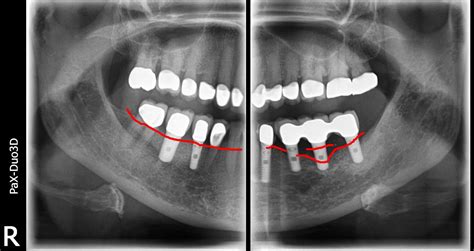

Dental professionals use various imaging techniques to determine the extent of Dental Bone Loss. The progression is typically categorized based on how much height or width the bone has lost. Below is a breakdown of how this impact is generally viewed:

Stage Description Clinical Impact

Early Minimal reduction in bone height Usually asymptomatic; visible on X-rays.

Moderate Noticeable loss of bone density Teeth may feel slightly loose or shift.

Advanced Significant loss of structure Visible facial sagging and high tooth mobility.

⚠️ Note: Regular dental check-ups with digital X-rays are the only way to detect the early stages of bone resorption before physical symptoms appear.